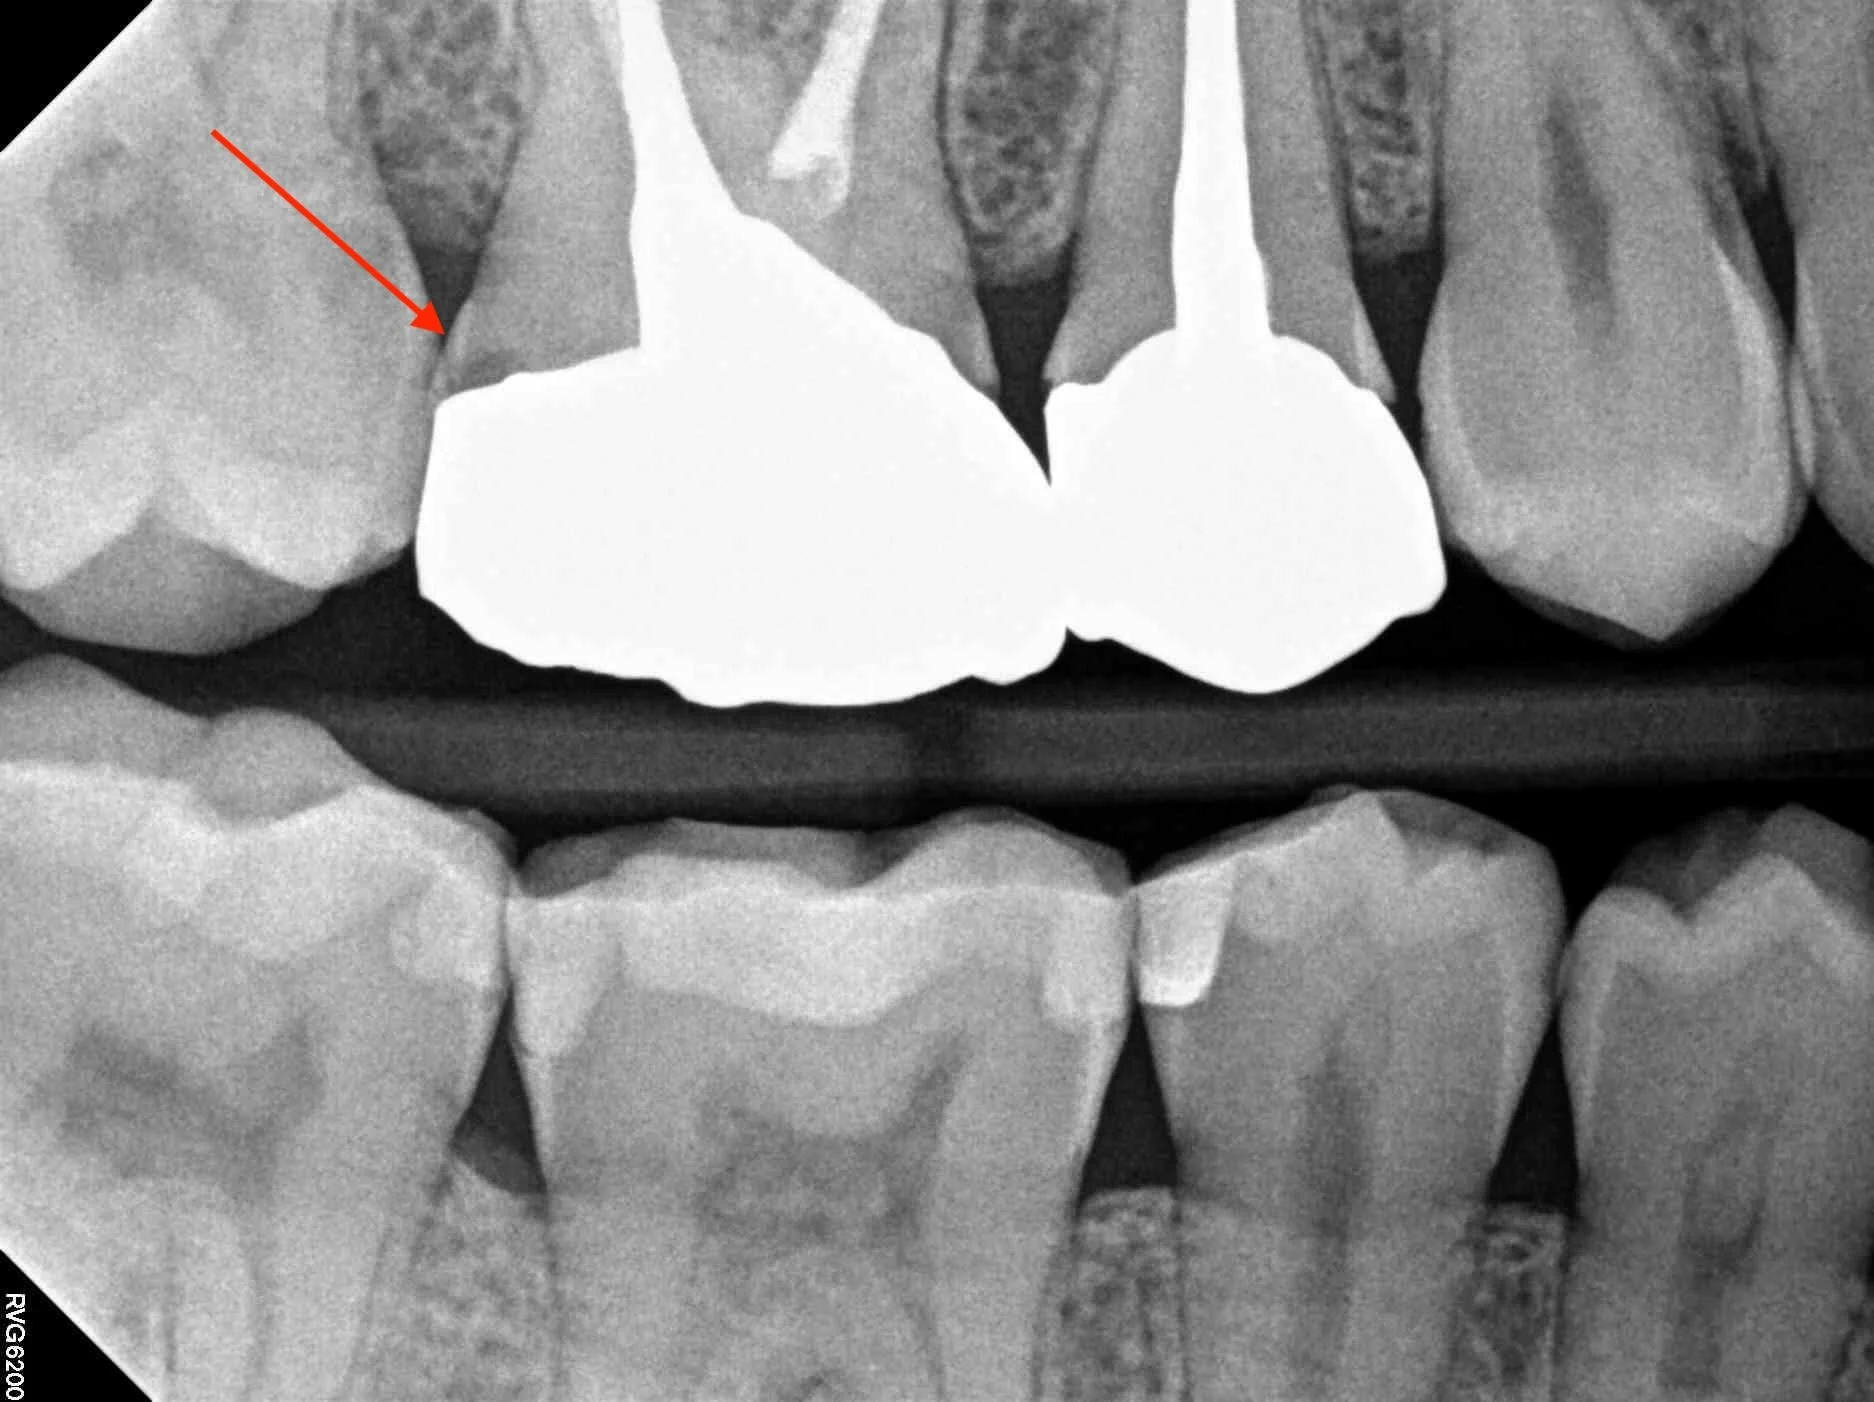

A tooth can appear completely fine on the outside while decay progresses underneath an onlay.

The red arrow shows a gap between this crown and the tooth which can indicate decay - The patient will not feel anything becuase the tooth has no nerve